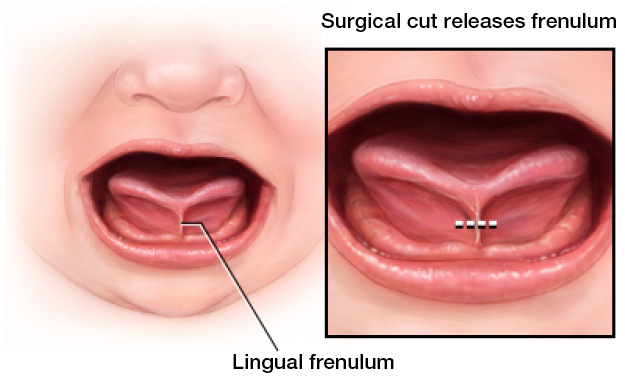

Minimally invasive release of tongue-tie and lip-tie restrictions to improve feeding, speech, breathing, and oral function.

State-of-the-art laser treatments for soft tissue procedures, tongue-tie release, and more — with faster healing and less discomfort.